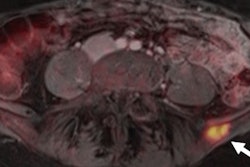

The value of PET/MRI continues to expand in the realm of women's imaging. German researchers have found that restaging breast cancer patients with the hybrid modality is superior to MRI alone. Also, they think the inclusion of MRI sequences such as diffusion-weighted imaging can extend scanning time with debatably beneficial results.

Overall, they endorse PET/MRI for its excellent diagnostic accuracy and diagnostic confidence for the identification of recurrent breast cancer lesions. Read how PET/MRI performs.